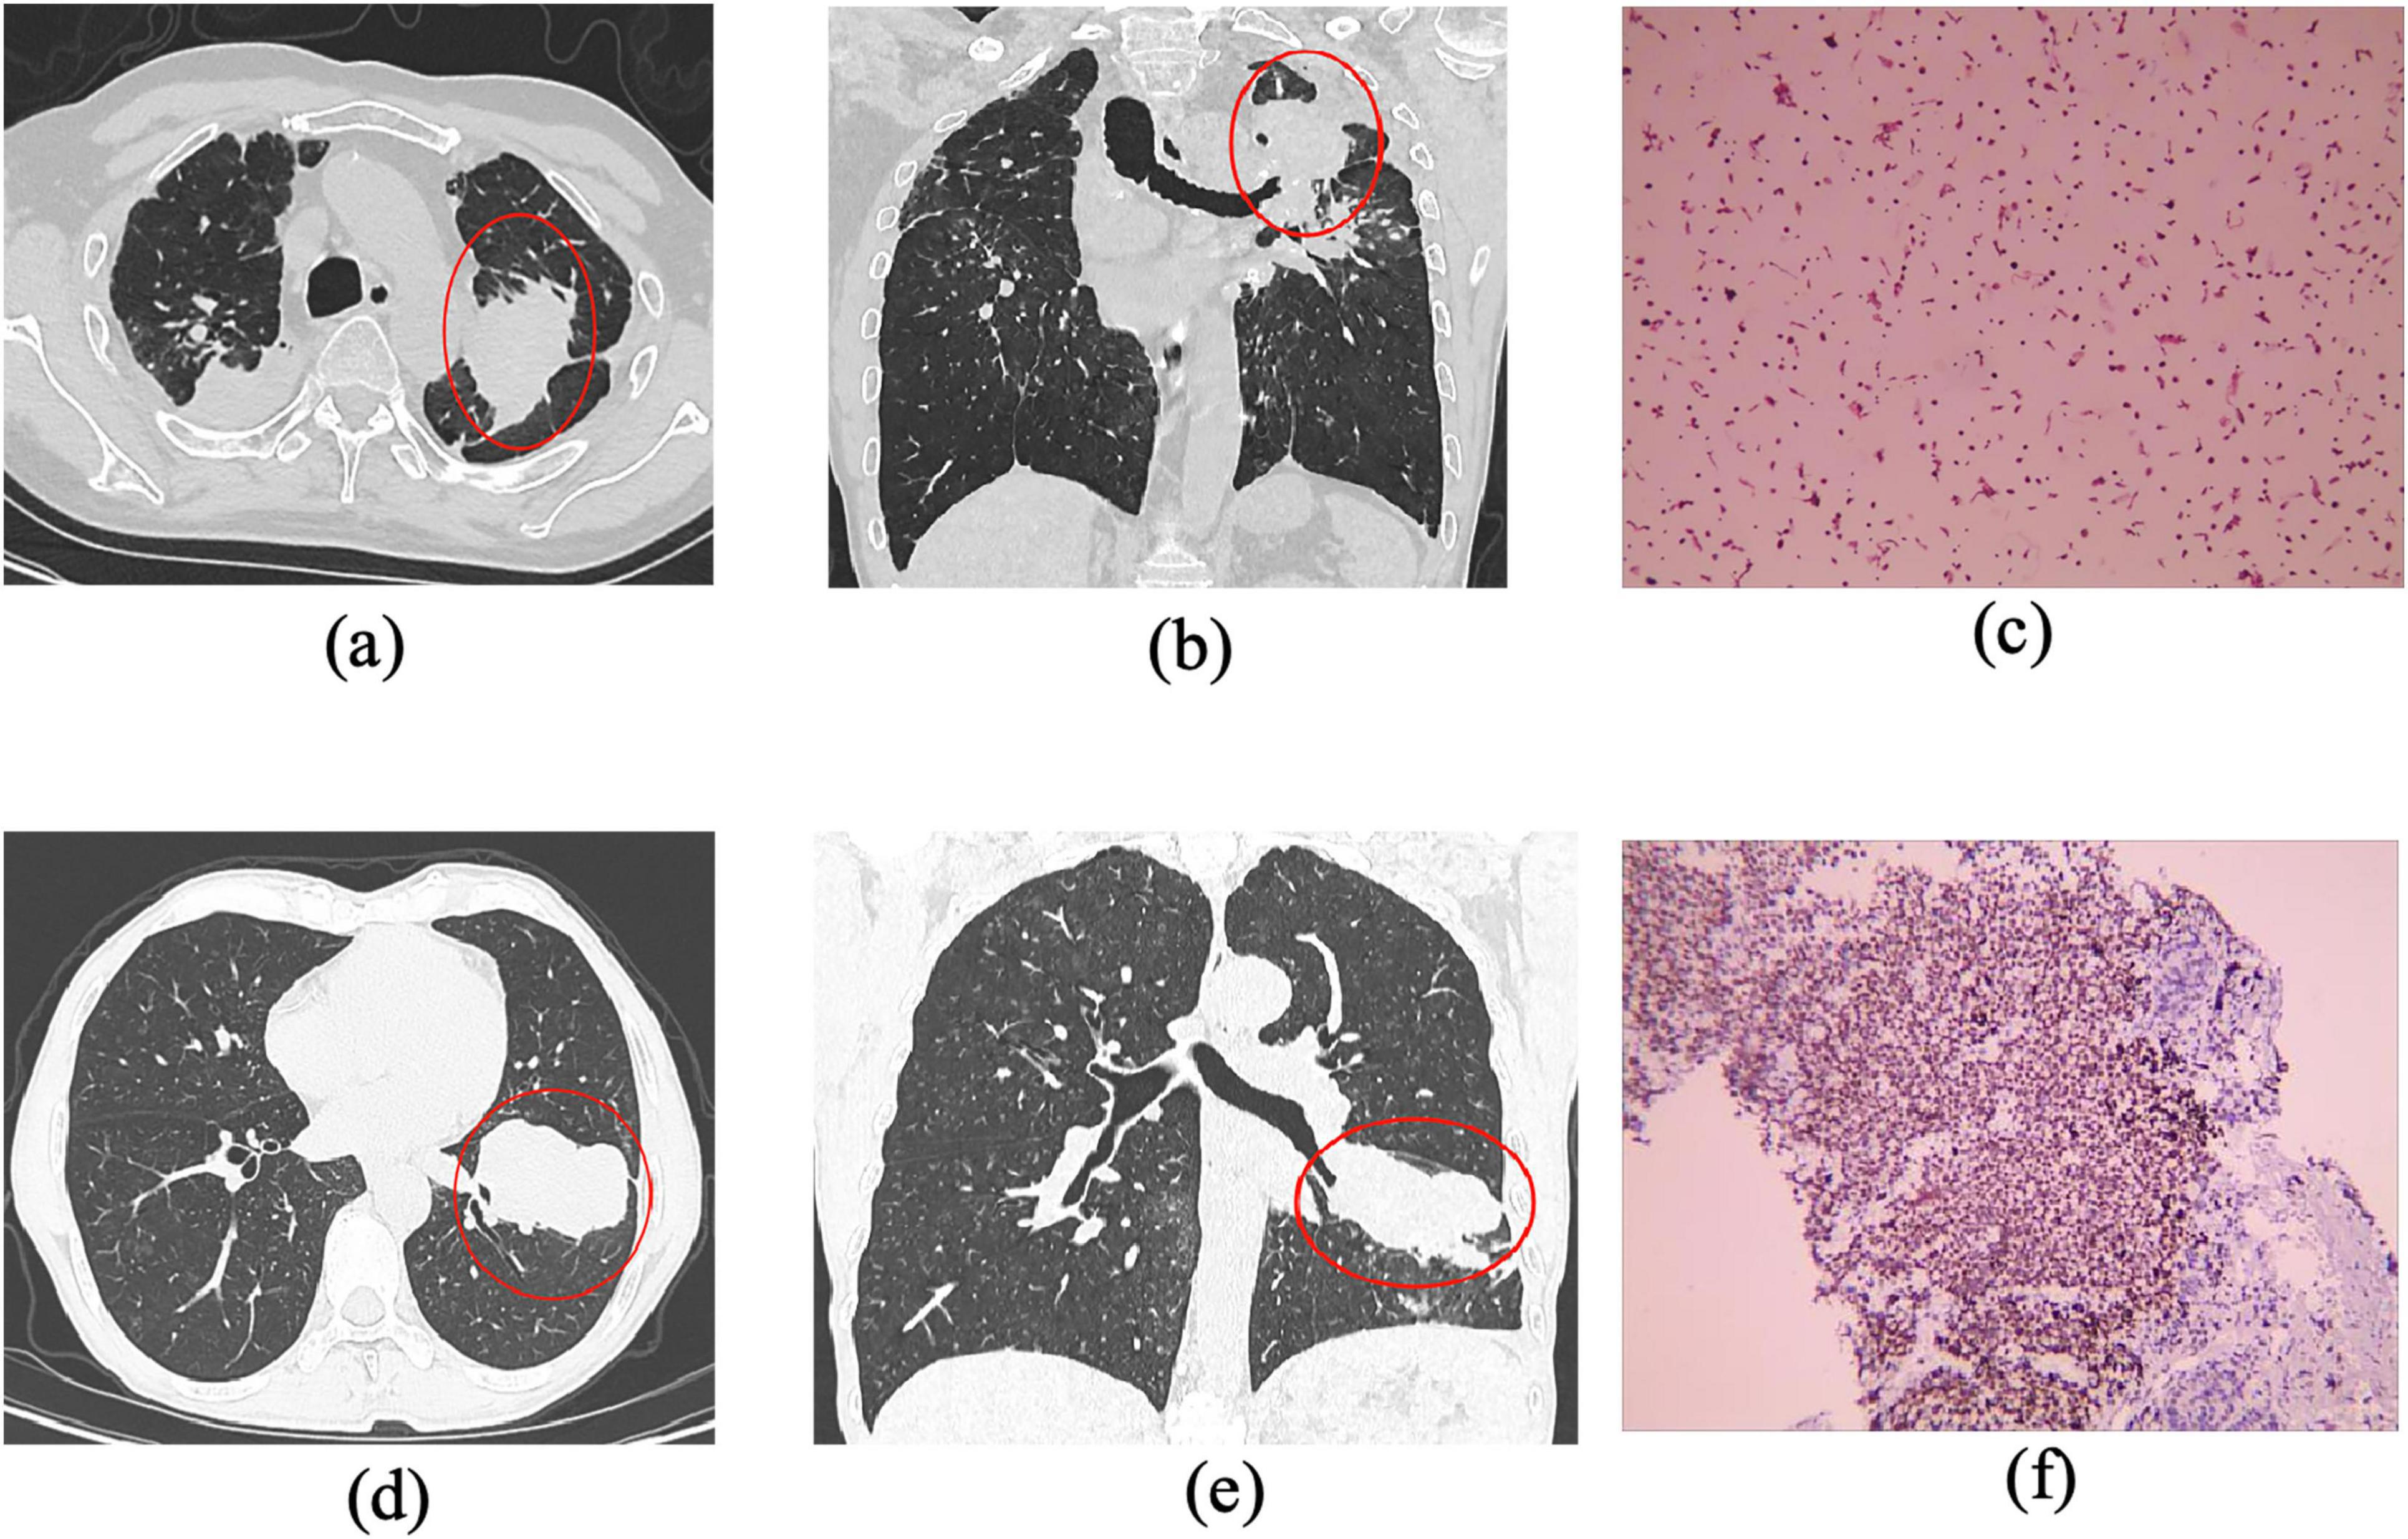

Inclusion criteria were as follows: (1) For the pneumoconiosis group: confirmed diagnosis of stage III pneumoconiosis with large opacities meeting the size thresholds (long-axis ≥ 20 mm, short-axis > 10 mm) (Figure 1; Supplementary Figure S1). (2) For the lung cancer group: confirmed diagnosis of peripheral lung cancer by both imaging and pathology, with lesions ≥ 30 mm in diameter (Figure 2; Supplementary Figure S2).

FIGURE 2

CT and histopathological features of pneumoconiosis-associated and malignant lesions in advanced pneumoconiosis. (a,b) Axial and coronal CT images of a Stage III pneumoconiosis patient, demonstrating bilateral apical mass lesions, with a dominant lesion located in the posterior segment of the left upper lobe (long-axis diameter > 20 mm, short-axis diameter > 10 mm). The lesion exhibits irregular margins, peripheral fibrotic strands, pleural thickening, and localized adhesion, along with partial truncation of the left upper bronchus. (c) The histopathological examination of the lesion, revealing a heterogeneous composition of epithelial cells and inflammatory infiltrates, predominantly macrophages (45%), lymphocytes (40%), neutrophils (10%), and a minor fraction of other cell types (5%). (d,e) Depict a large, multilobulated mass in the posterior segment of the right lower lobe, showing pleural retraction and areas with ill-defined borders. (f) Demonstrates immunohistochemical (IHC) staining results, confirming the presence of a malignant neoplasm with focal necrosis. The tumor cells were partially positive for cytokeratin (CK), weakly positive for chromogranin A (CgA) and synaptophysin (Syn), partially positive for INSM1, and sporadically positive for CD56, collectively supporting a diagnosis of neuroendocrine carcinoma.